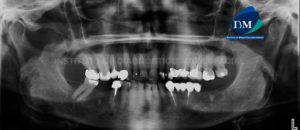

Paciente femenino de 24 años de edad, es referido al Instituto de Diagnóstico Maxilofacial – IDM por accidente. En la radiografía panorámica (Figura 1) se